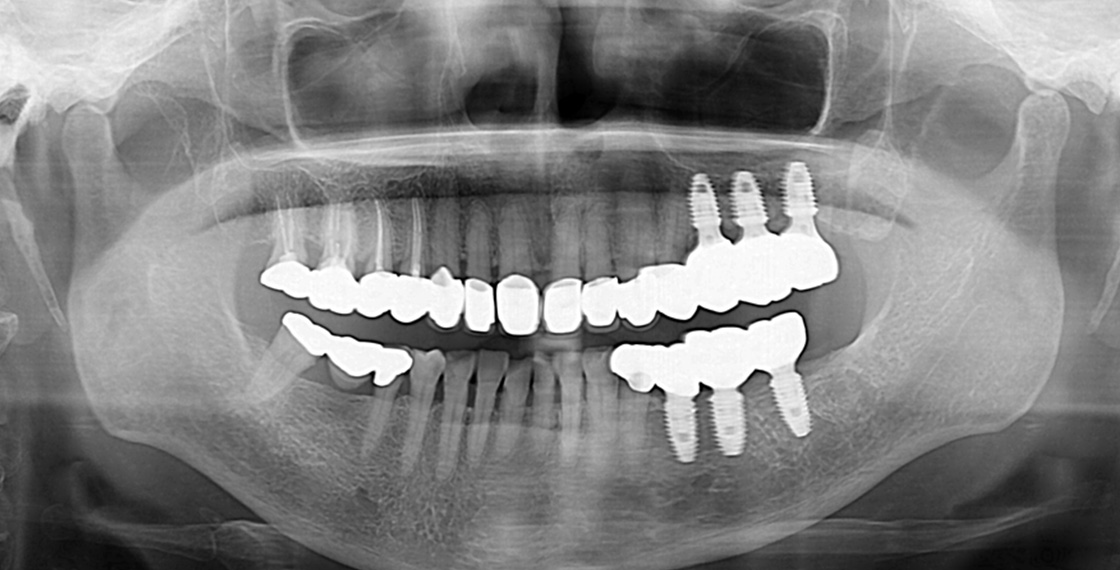

네비게이션 수술 사례

03

잇몸 절개를 최소화 해서,

통증이 없고, 빠른 수술이 가능합니다. -

04

수술 당일 바로

일상 생활이 가능합니다. -

네비게이션 수술

수술 당일 티 안나는 보철 치료 가능